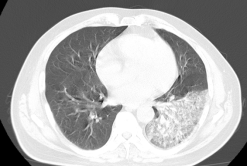

患者李先生,今年58岁,平时收购废弃钢材和塑料,10月27日因发热伴咳嗽、呼吸困难入住我院呼吸与危重症一科,入院时神志欠清,测体温39.4℃,血压87/56mmHg,末梢血糖26mmol/L。入院后,立即予完善相关检查,血气分析提示I型呼吸衰竭,胸部CT检查提示左肺大叶性肺炎伴实变,提示重症肺炎、感染性休克,种种迹象表明,患者病情危重,若不及时采取处理,随时可危及生命。

在科室主任王士汉医师的指导下,立即在抗感染、补液扩容升压、控制血糖的基础上,进行支气管镜灌洗液mNGS检查,进一步明确病原体为嗜肺军团菌。在予以敏感抗菌药物治疗后,患者体温、血压、氧合逐步恢复正常,炎性指标下降至正常,临床症状明显好转,并于11月8日顺利出院。